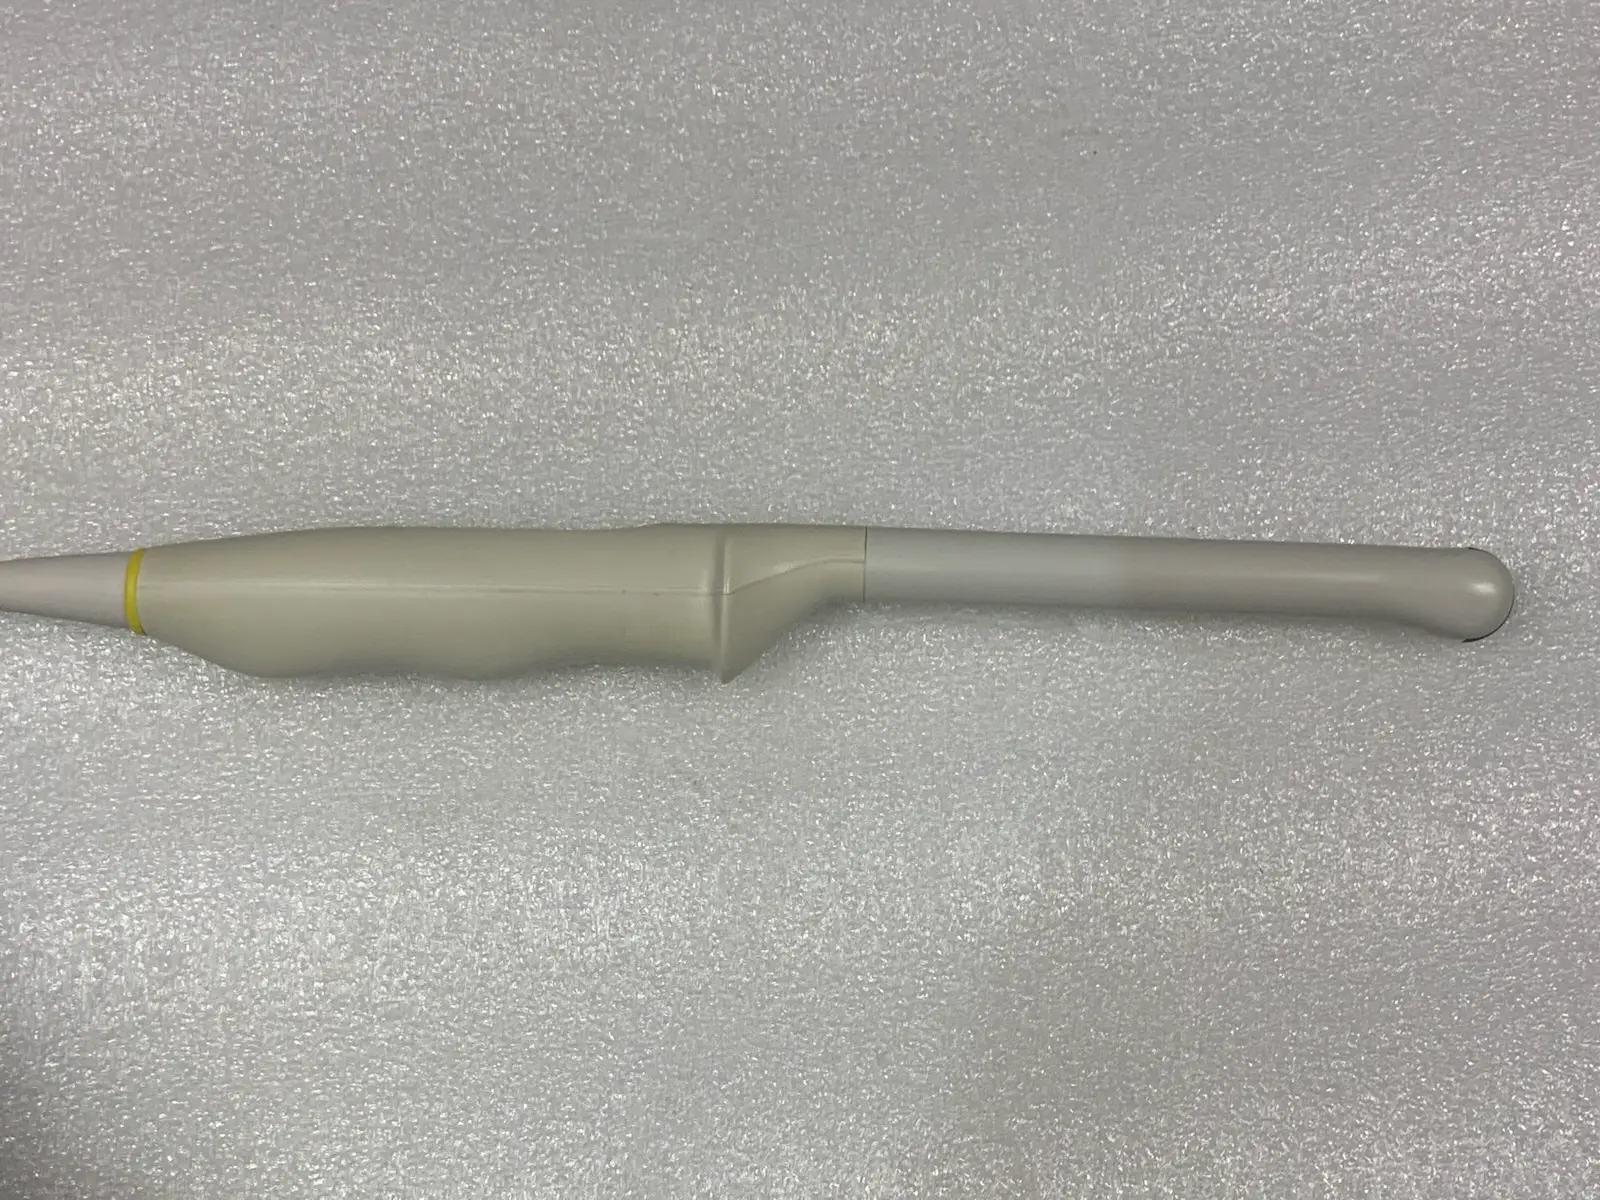

Up for sale is a genuine Mindray V10-4s curved array endocavity probe. This transducer is designed for high-resolution imaging in obstetrics, gynecology, and urology. It features a wide-band frequency range (4–10 MHz) and a small 10mm radius for patient comfort.

Acoustic Window (Lens): Appears clean and intact with no significant delamination or pitting visible in photos.

Photos of this listing are of the actual item for sale.